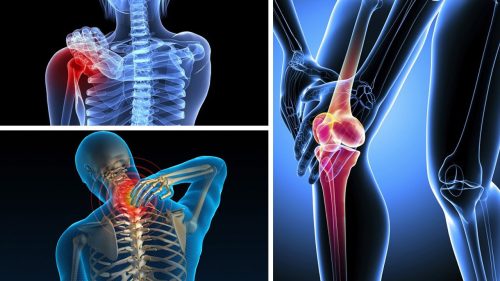

Bệnh cơ xương khớp bao gồm một loạt các tình trạng ảnh hưởng đến cơ, xương, khớp và các mô liên kết khác. Các bệnh này có thể gây ra đau đớn, viêm, cứng khớp, và hạn chế khả năng vận động của người bệnh. Một số bệnh cơ xương khớp phổ biến bao gồm viêm khớp dạng thấp, thoái hóa khớp, viêm gân, bệnh gút, loãng xương, và các bệnh cơ bẩm sinh.

- Viêm khớp dạng thấp: là một bệnh tự miễn, khi hệ miễn dịch tấn công nhầm vào các mô khớp, gây ra viêm, đau và sưng. Nếu không được điều trị kịp thời, bệnh có thể dẫn đến biến dạng khớp và mất chức năng.

- Thoái hóa khớp: Là quá trình thoái hóa tự nhiên của sụn khớp do tuổi tác, chấn thương hoặc sử dụng quá mức. Biểu hiện chính của bệnh là đau và cứng khớp, thường gặp ở các khớp chịu lực như khớp gối, khớp hông và cột sống.

- Viêm gân: Là tình trạng viêm của các gân, thường do chấn thương hoặc sử dụng quá mức. Viêm gân thường xảy ra ở các khớp lớn như vai, khuỷu tay, cổ tay và gót chân.